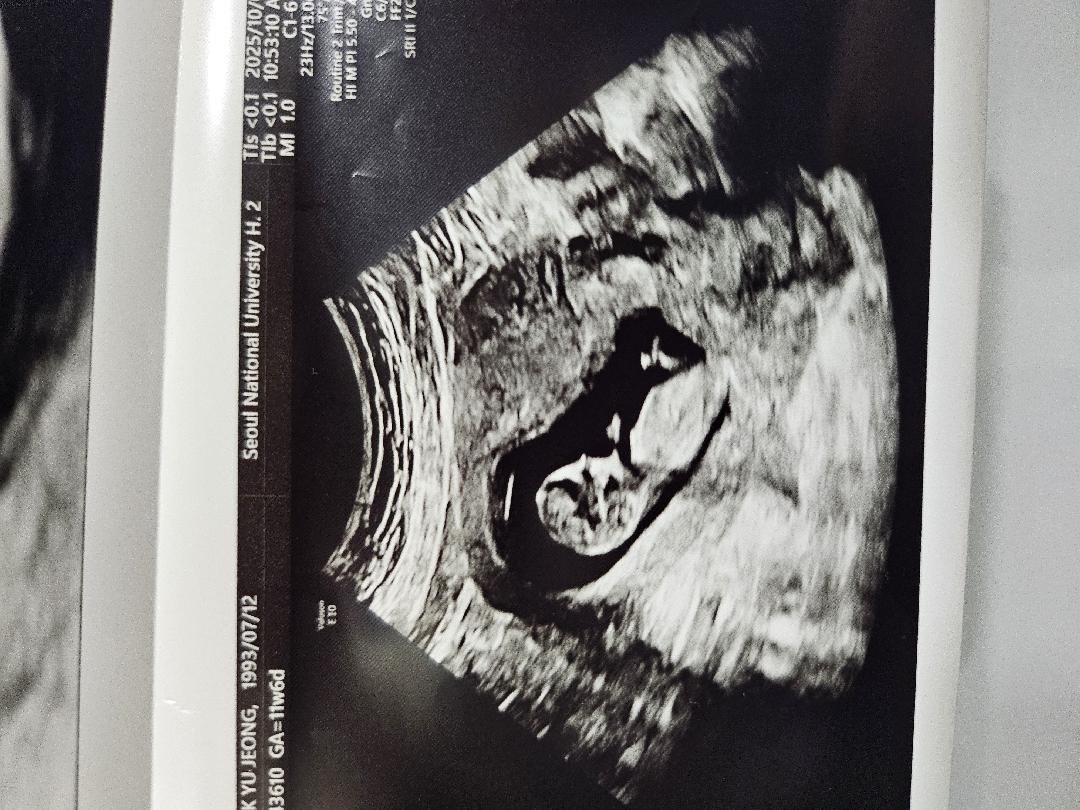

각도법 좀 봐주세요!

11주6일차인데 아들일까요 ,딸일까요?